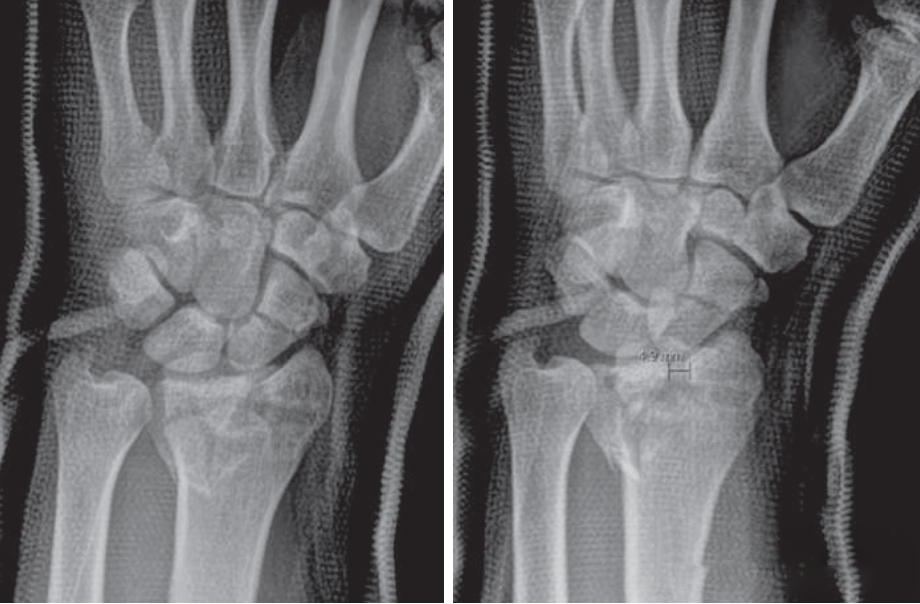

«Золотой стандарт» хирургии: внутренняя фиксация ладонной блокирующей пластиной подхода Генри для ле

Перелом дистального отдела лучевой кости является наиболее частым переломом верхней конечности, на его долю приходит···